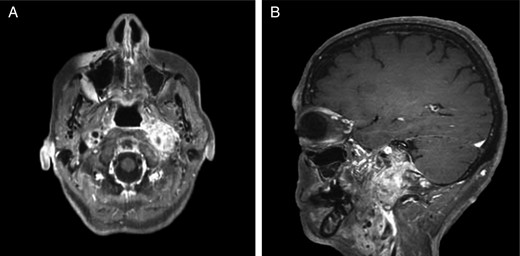

Repeat magnetic resonance imaging (Figs. 3 and 4) showed increased left-sided carotid PGL, significant extension into the jugular foramen and skull base, and associated high-grade tumor compromise of the left internal carotid artery; no radiologic evidence suggested intracranial ischemic sequelae. Computed tomographic (CT) imaging showed infiltration of the left petrous and clivus regions of the skull (Fig. 5). Findings were compatible with progression of the previously known tumor.

(A and B) Magnetic resonance images, sagittal and coronal planes, show increased left-sided carotid PGL, with significant extension into the jugular foramen and skull base.